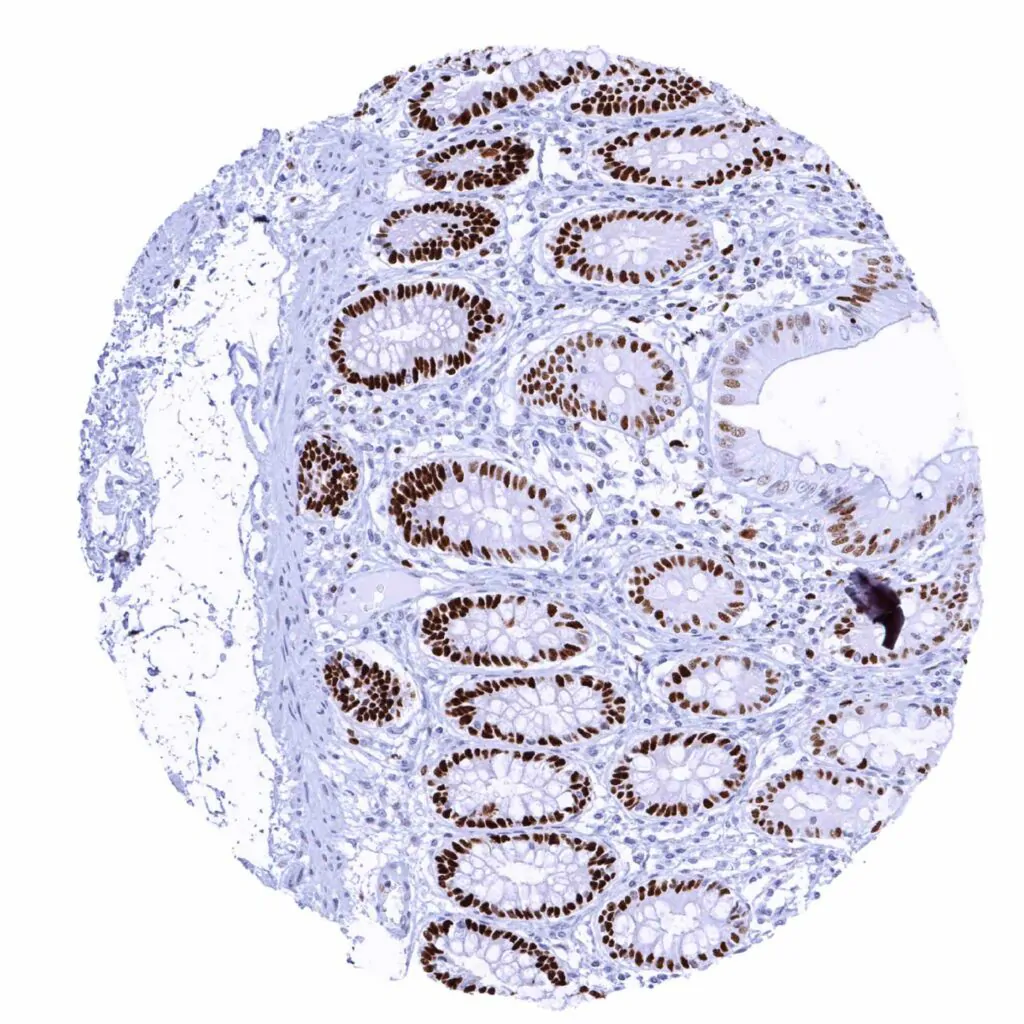

Colon descendens, mucosa – MCM2 staining predominates in epithelial cells of the crypts